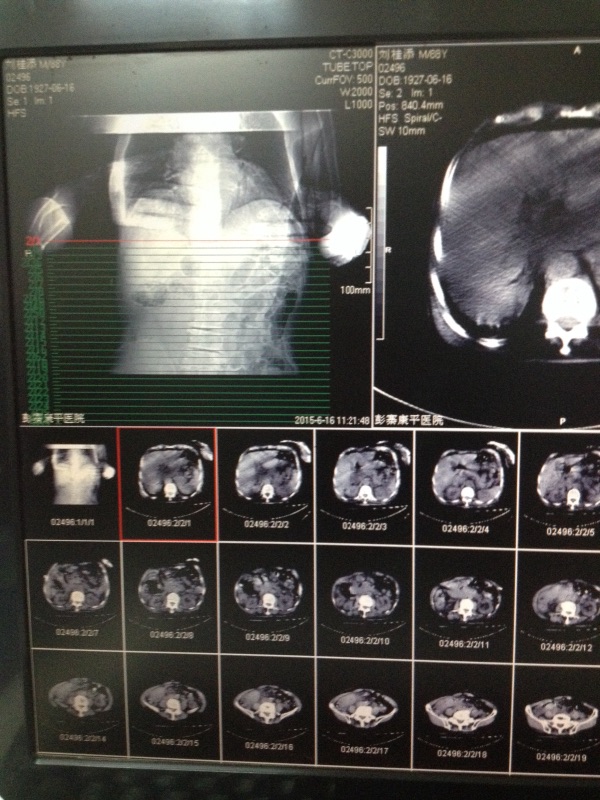

CT59710:下腹部,请看一下。

寒战高热男,88岁,寒战高热。请看一下。图像质量不是很好,请见谅。

首先考虑升结肠癌,炎性病变不除外建议结肠肠结肠。

结肠癌部分肠套叠

阑尾脓肿

占位